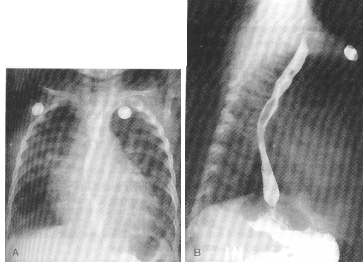

Fig. 6.1. Comunicação interventricular. A. Visão póstero-anterior. Note a vascularização pulmonar aumentada. Há moderadas cardiomegalia e dilatação ventricular esquerda, que produzem uma queda descendente ou inclinando-se do ápice cardíaco. Aumento atrial esquerdo também está presente. B. Visão lateral. O deslocamento posterior e a indentação do esôfago, associados com aumento atrial esquerdo, são visíveis.